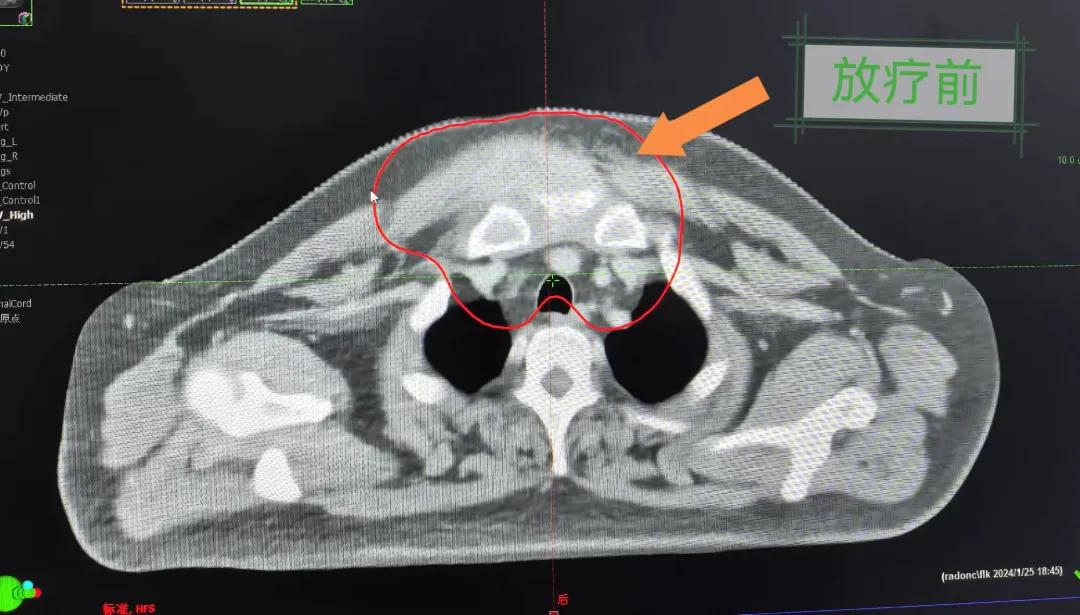

隨后,趙亮主任帶領(lǐng)放療團(tuán)隊(duì)以最快的速度完成了患者的放射治療計(jì)劃,在保證放療精準(zhǔn)打擊腫瘤的同時(shí),利用先進(jìn)的三維立體精確放療技術(shù),最大限度的避免心臟、肺部的損傷發(fā)生,整體治療精準(zhǔn)度達(dá)到1mm以內(nèi)。經(jīng)過(guò)10次的放射治療后,患者疼痛已明顯減輕,胸部腫物肉眼可見(jiàn)的縮小,患者及家屬臉上終于露出久違的笑臉。

治療期間,患者沒(méi)有出現(xiàn)明顯不適,治療結(jié)束后,患者胸壁腫物由最初8cm縮小至約1cm,后患者至外科行手術(shù)治療。